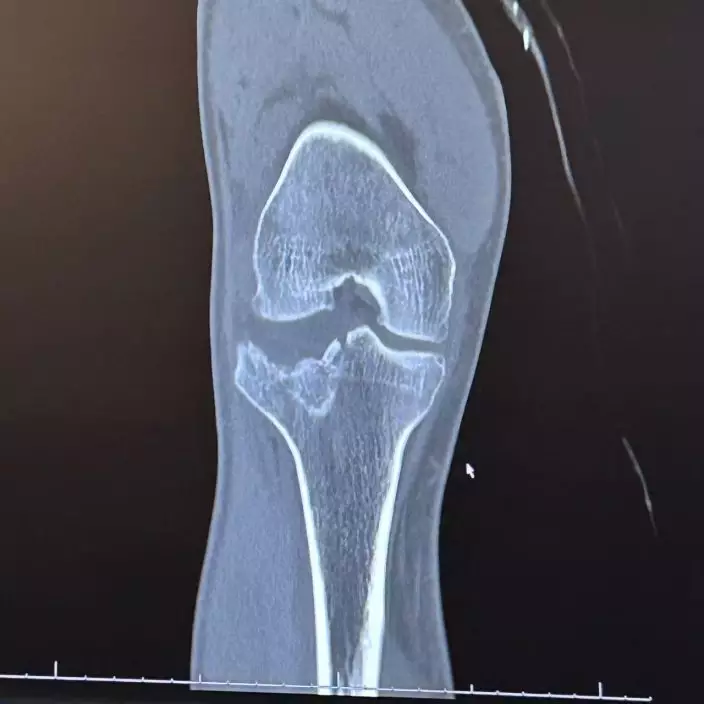

哈里斯被救出時已出現腿部骨折及嚴重失溫情況,同時伴隨肺炎、肺部挫傷及腎臟受傷等傷勢,隨即被送往醫院接受治療,目前仍在康復中。親友事後於募款網站上表示,哈里斯已完成手術,恢復情況良好,並感謝外界的關心與支持。哈里斯也透露,事發時自己的手機其實就在身旁,但始終無法伸手取得。他直言,若非妻子透過定位功能追蹤位置並及時求助,自己很可能已經無法生還。